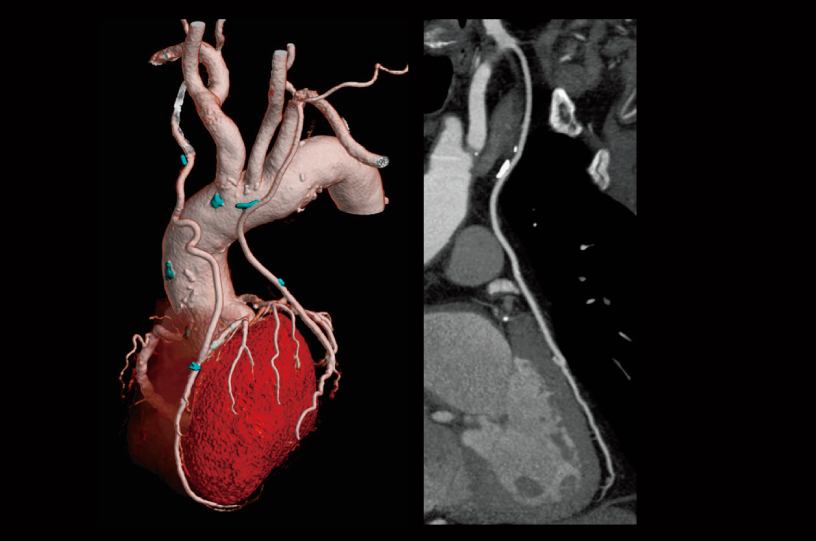

Seguimiento después de la colocación del stent LAD

- * Las imágenes distintas a las imágenes axia fueron procesadas por el sistema de análisis de imágenes 3D de SYNAPSE 3D.